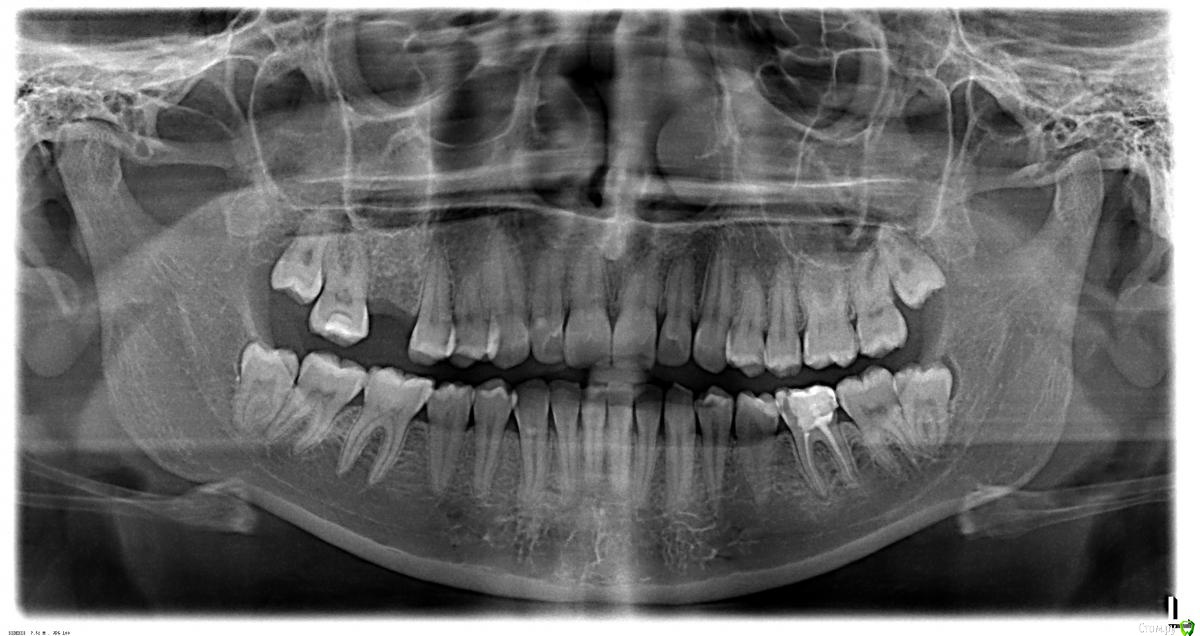

L_Z Опубликовано 12 апреля, 2015 Поделиться Опубликовано 12 апреля, 2015 Добрый день!Ситуация следующая:После удаления 6-ки справа сверху я заметила, что 6-ка слева доставляет дискомфорт (сразу оговорюсь - до удаления 1-го в жизни зуба не парилась вообще на эту тему), пошла к доктору - сказал, в зубе трещина, если не ушла в корни, то восстанавливать коронкой, но на снимке ничего не видно, и покажет только вскрытие. Решила сходить еще к специалистам - в одной клинике обещали отрестврировать шикарно, второй доктор предложил коронку без перелечивания каналов.В общем, в тот момент я растерялась от обилия информации и оставила этот момент на 4,5 месяца.Спустя это время один из врачей, у которого я была и вернулась к нему, потому что он залечил прекрасно 5-ку, сказал, что откололся кусочек (я этого не заметила) и покажет только вскрытие. У него же я хотела делать имплант, но он их не делает.Пришло время, когда можно делать имплант, мне посоветовали врача, я пришла и он уже мне все описал,в том числе и про 6-ку снизу. смотря на ортопанораму, что будем делать культевую вкладку, мы договорились о времени, и в назначенный день, на осмотре, он сказал тоже, что судя по моим ощущениям, мог треснуть корень, и лучше тогда не трогать, если я не готова удалять. (Я не готова). Делать имплант послал к другому доктору, но это отдельная история, в итоге я отказалась, перепугалась, потому что мне было предложено удалить зубы мудрости одновременно на стороне 6-ки, куда ставить имплант. Зубы мудрости ретинированные., все это под седацией.Честно говоря, голова уже пухнет, все врачи по рекомендациям, но ничего конкретного по 6-ке снизу этой не говорят.Я понимаю, что все можно сказать только очно, но хотелось бы ваших мнений.Я очень надеюсь, что ее можно восстановить коронкой на вкладке, сама виновата, но имплантов пока боюсь, мост не вариант, а лишиться двух жевательных в 26 лет очень печаль. Если этот снимок что-то даст, помогие советом, пожалуйста. Ссылка на комментарий

DmitrySH Опубликовано 12 апреля, 2015 Поделиться Опубликовано 12 апреля, 2015 36 - требуется ревизия каналов ( на снимке признаки хронического воспаления) желательно чтоб под контролем микроскопа, для исключения трещин.И после этого ортопедическое восстановление, Вкладка +коронка 1 Ссылка на комментарий

krokomot Опубликовано 12 апреля, 2015 Поделиться Опубликовано 12 апреля, 2015 Тогда не заморачивайтесь перелечивайте каналы и протезируйтесь, наличие трещины корня не всегда я вляется показанием к удалению а вот без перелечивания и перекрытия коронкой зуб может развалиться итог,1. лечить каналы под микроскопом2. корневая штивтовая конструкция 3. коронка,4. в область удаленного зуба имплант Ссылка на комментарий

Гарриевич Опубликовано 12 апреля, 2015 Поделиться Опубликовано 12 апреля, 2015 Зубы мудрости сейчас удалять не обязательно, но рано или поздно придется все равно36 зуб перелечивать + вкладка+ коронкаТрещины в пределах эмали (Вы скорее всего видите их) не опасны Ссылка на комментарий

DmitrySH Опубликовано 12 апреля, 2015 Поделиться Опубликовано 12 апреля, 2015 Убрать пломбу и посмотреть внутри.На КТ трещины не видно.8-е не мешают имплантации . Ссылка на комментарий